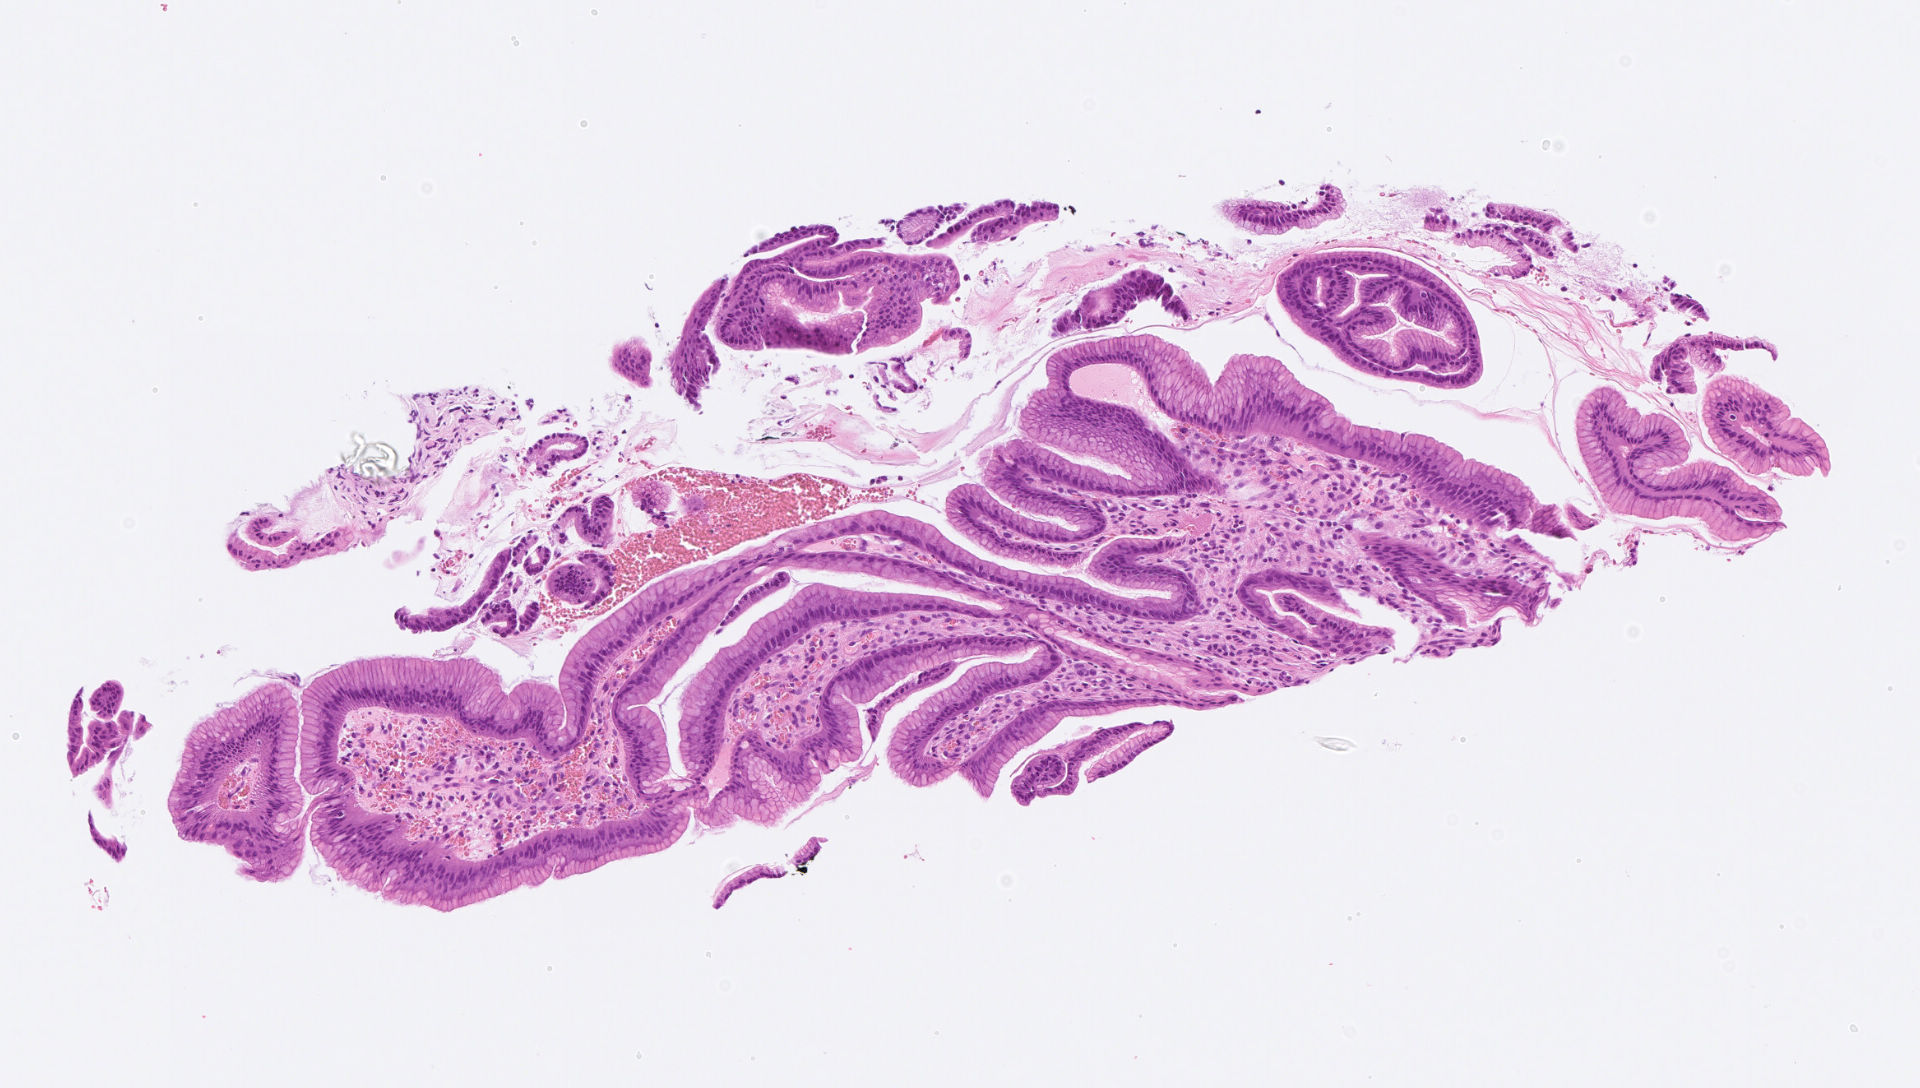

My stomach biopsy

あなたの診断は?